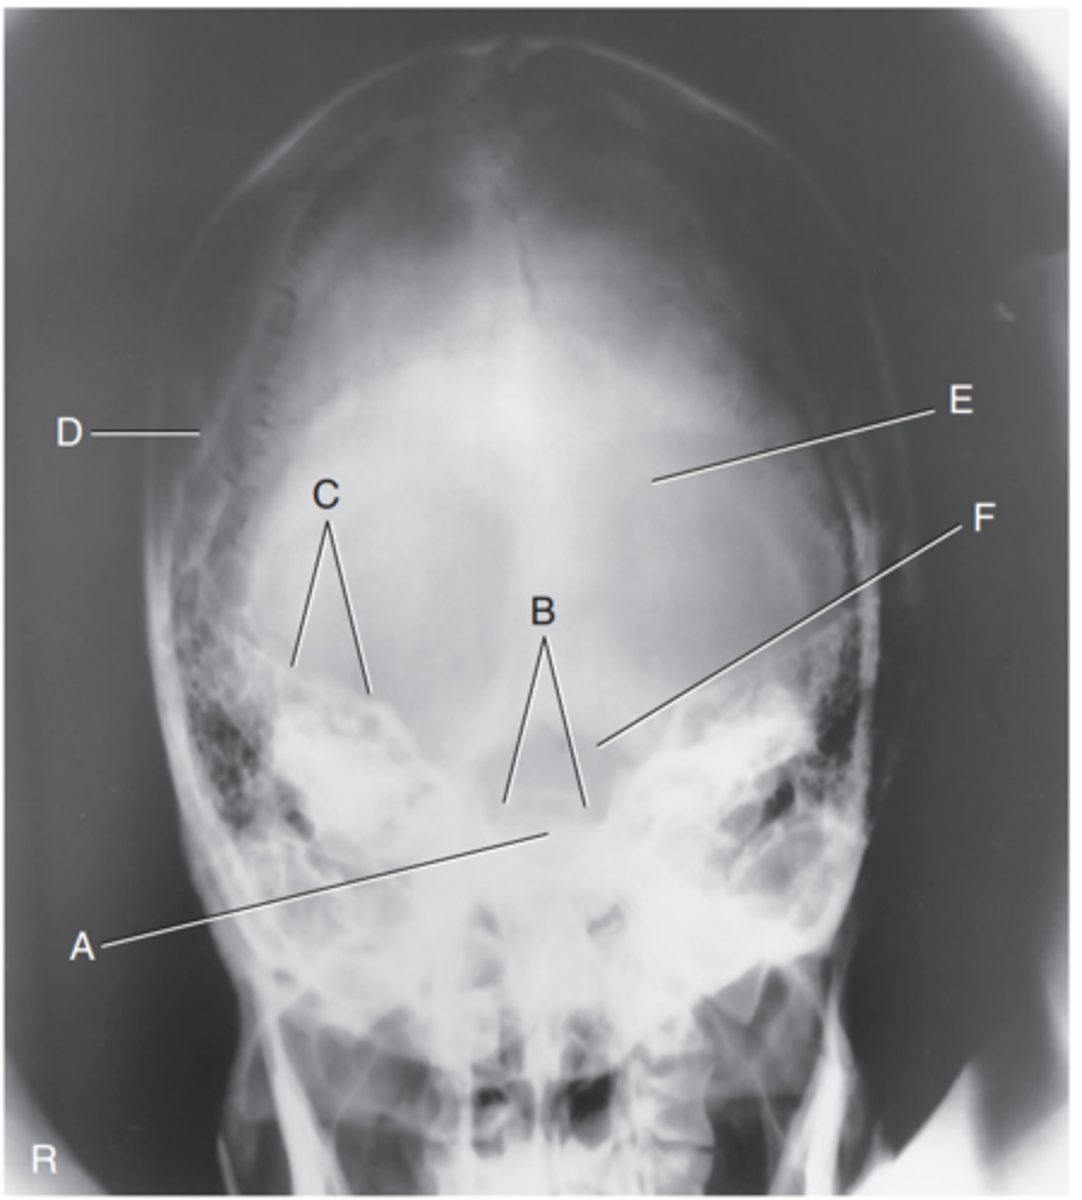

Supraorbital margin of right orbit

Label A

Crista galli of ethmoid

Label B

Sagittal suture

Label C

Lambdoidal suture

Label D

Petrous ridge

Label E